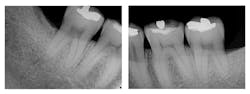

Figure 2: Six-month post-treatment radiographs and photos

Evaluation-A six-month evaluation demonstrated reattachment (see Figure 2). The radiograph of tooth No. 18 exhibited 7.4 mm bone loss on the distal surface, reflecting an increased bone height of 4.4 mm. For tooth No. 31, the radiograph exhibited 6.2 mm bone loss, reflecting an increased bone height of 2.2 mm. Epithelial attachment gain was clinically evident as well (see Table 2). Pocket depths had marked improvement with elimination of furcation involvement on both teeth, decreased mobility of tooth No. 18, and no increase in recession. The patient also submitted three-year post-treatment radiographs taken by the dental hygienist of record (see Figure 3) with evidence of bone stability.